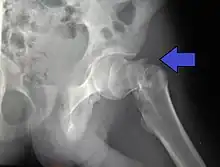

![]() | |

| Intertrochanteric hip fracture in a 17-year-old male | |